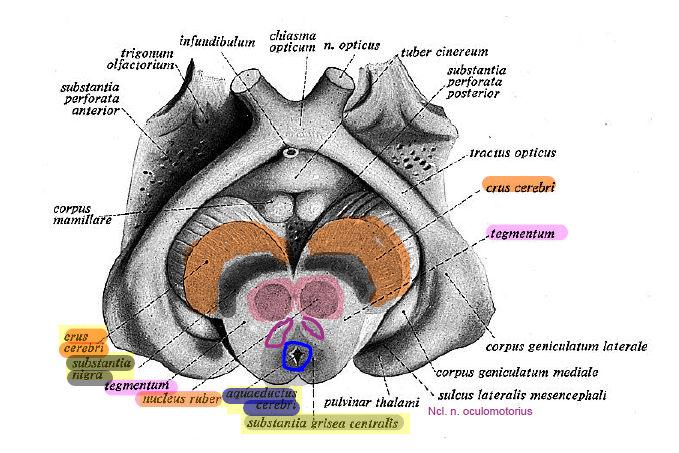

Необычные объекты: Переднее продырявленное вещество

Раздел: Альбом открытий